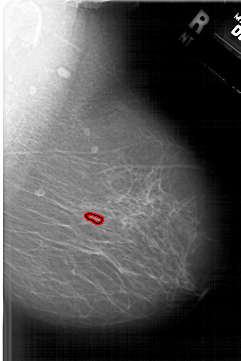

A_1633_1.RIGHT_CC

RIGHT_CC LINES 6436 PIXELS_PER_LINE 3886 BITS_PER_PIXEL 12 RESOLUTION 43.5 OVERLAY

FILE: A_1633_1.RIGHT_CC.OVERLAY

TOTAL_ABNORMALITIES 1

ABNORMALITY 1

LESION_TYPE CALCIFICATION TYPE PLEOMORPHIC DISTRIBUTION CLUSTERED

ASSESSMENT 4

SUBTLETY 3

PATHOLOGY BENIGN

TOTAL_OUTLINES 1

BOUNDARY